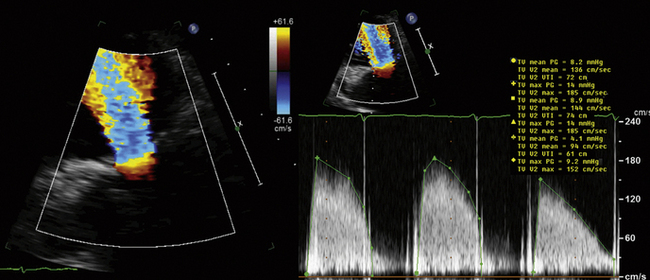

Obtain the complete TR profile by appropriate means, and measure in the center of the parabola. The single most common problem with TR spectral recording is not having enough signal to establish the true peak velocity. If the complete profile does not appear to be present, the cursor should be placed off to the side of the profile so that the reviewer is not swayed by the position of the cursor placed by the person recording the study.

Spectral profiles should be two-thirds the height of the display, and wide enough so that there are two or three per display.